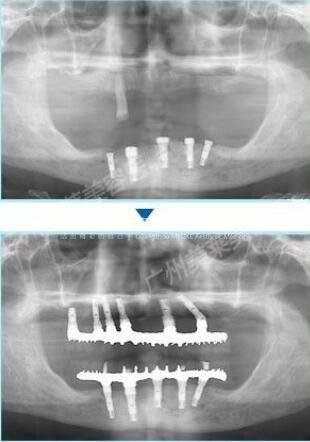

廣州美萊的口腔醫(yī)生團(tuán)隊(duì),為她打造了全口種植牙方案,拔牙、種植牙一起完成,上下各種植了8顆牙。

種植牙前后對(duì)比圖